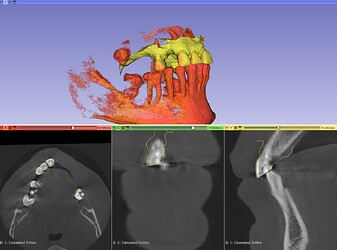

3D Slicer Rendering: Sharper Dental Views Rendering in 3D Slicer isn’t cinematic, but for dentistry it’s more than enough. I’ve tested several presets — “3D

3D Slicer Implantology: Plan Smarter Planning implants digitally sounds fancy, but honestly it’s become the norm. I remember trying 3D Slicer for the first time